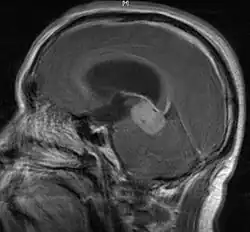

• Mainly located in midline structures, suprasellar region or pineal gland, also basal ganglia and hypothalamus

• Bifocal germinomas (synchronous suprasellar and pineal tumors) regarded as M+ in USA but M0 in Europe

Location